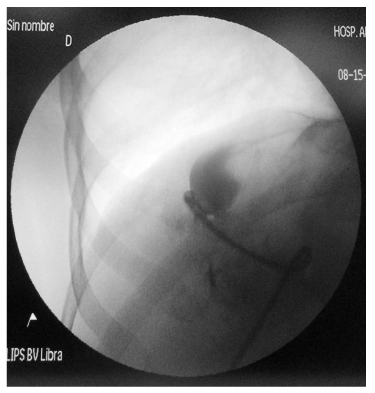

El tratamiento con el que se inicia es el drenaje percutáneo del quiste hepático de mayor tamaño (114 x 94 x 105 mm en el segmento hepático VIII), utilizando guía tomográfica y técnica de Seldinger; se obtienen 300 cc de líquido seroso y se deja catéter de 8 french a nivel del quiste (Figuras 4 y 5). Una semana después del procedimiento se realiza la escleroterapia (alcoholización) del quiste, procedimiento que se lleva a cabo en quirófano bajo sedación y utilizando ecografía y fluoroscopía: a través del catéter de instila contraste hidrofílico y con ayuda de fluoroscopía se comprueba que el quiste no tiene comunicación con la vía biliar (Figura 6); paso seguido se introduce a través del catéter alcohol de 70 grados durante un minuto y se retira el alcohol. Con ayuda ecográfica se comprueba la indemnidad de la vía biliar; luego de cinco días se retira el catéter. La evolución clínica es favorable, con alivio completo de los síntomas después de la intervención.